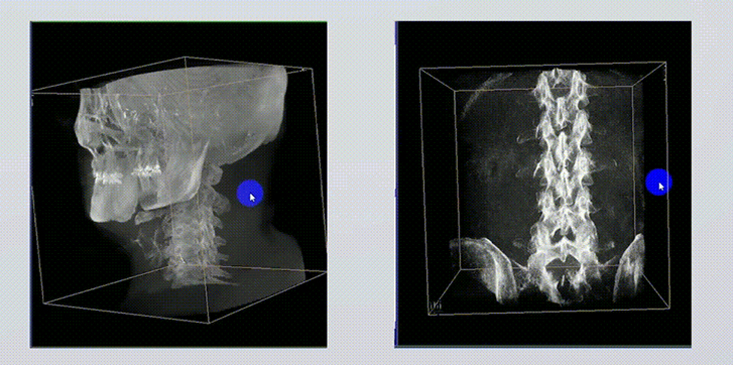

1、術中實時三維成像

術中三維成像和橫斷面圖像提供多角度的手術診斷信息,輔助醫生進行術中評估判斷,諸如骨折復位情況和內植入螺釘的尺寸和位置,輔助手術更好地完成。

提供更大的術中三維成像視野,采集更多圖像信息,可一次拍全全段頸椎、全段腰椎、七節胸椎、雙側骶髂關節、股骨頭及單側盆骨。